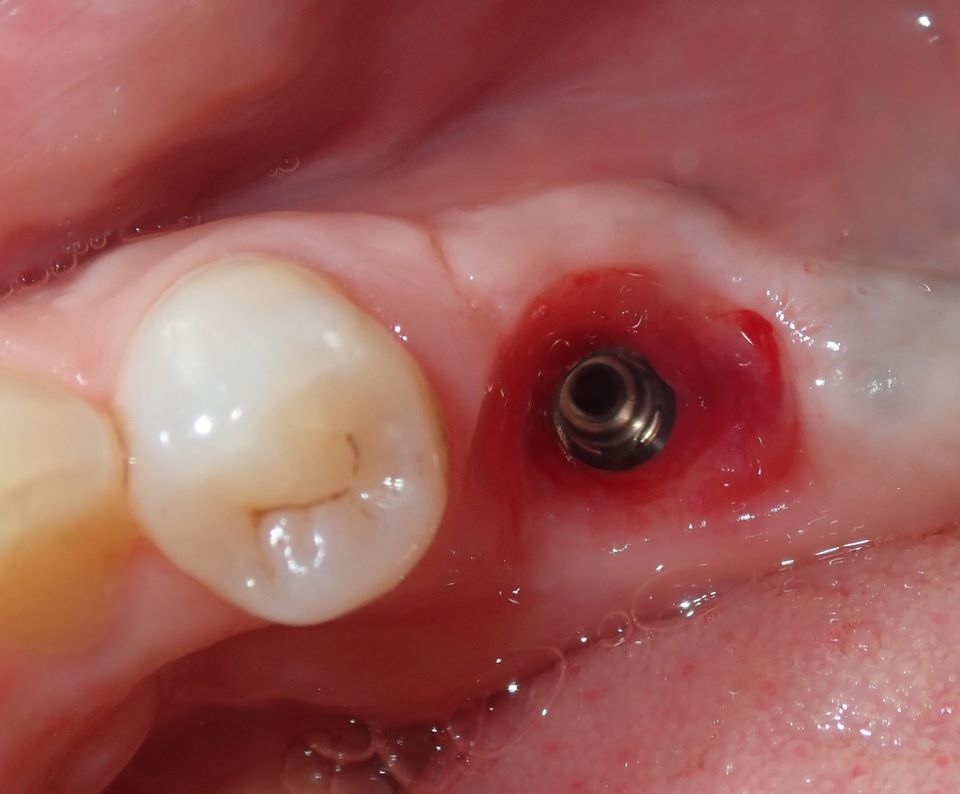

A 4.8 mm x 10 mm implant (Straumann® Bone Level Tapered [BLT], Straumann) had been placed at the mandibular first molar site and was ready for restoration. A custom healing abutment was fabricated and inserted at the time of surgical implant placement and soft tissue was sutured around the abutment using 4/0 Glycolon sutures (Osteogenics Biomedical, osteogenics.com) (Figure 13). A periapical x-ray was taken at the time of placement of the custom healing abutment to confirm full seating (Figure 14).

Fig 13. A custom healing abutment was created to replicate the emergence profile for a mandibular molar, which is square in cross-section.

Figure 13

Fig 14. A periapical radiograph of the custom healing abutment on the implant demonstrated the development of a natural emergence profile for a mandibular molar to replicate the missing natural tooth.

Figure 14